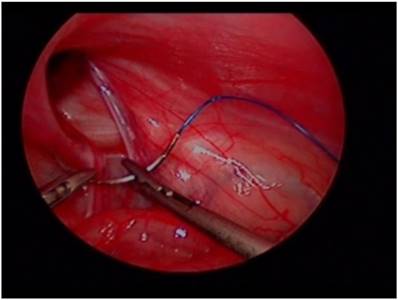

Fig 2

Laparoscopic view of purse-string repair.

Patients underwent surgery with pelvis slightly elevated in supine position. A 5 mm, 30° angled laparoscope was inserted above or through the umbilicus. We maintained an 8mmHg pressure for pneumoperitoneum, confirmed unilateral hernia, and evaluated contralateral side processus vaginalis opening. Two 2.7 mm laparoscopic needle holders were inserted into both abdominal sides at the level of umbilicus. The internal opening of inguinal hernia was then ligated using a purse string suture method. In the case of the opposite-side PPV, it was sutured using the same method (Fig. 1, Fig. 2). Contralateral PPV repair indication was: depth of PPV > 1 cm, no relation with diameter of PPV or shape.